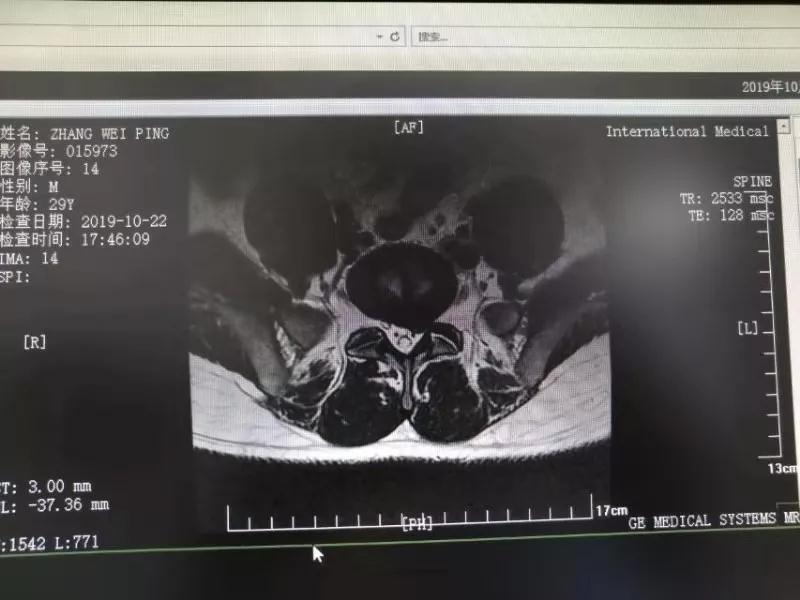

10月25日,29歲的患者小張了解到西安國(guó)際醫(yī)學(xué)中心骨科醫(yī)院專家云集,一大早便在家人的陪同下,來(lái)到西安國(guó)際醫(yī)學(xué)中心骨科醫(yī)院就診?!拔已闯掷m(xù)2年多,最近感冒后腰痛癥狀明顯加重了。”小張面露苦楚,因?yàn)殚L(zhǎng)期腰痛、左下肢放射性疼痛,她晚上睡覺不能平躺,經(jīng)常疼得睡不著,需要口服止痛藥物才能有所緩解。走路走不了多遠(yuǎn)就開始腿抽的疼,嚴(yán)重影響到工作和生活。

結(jié)合患者的檢查以及年齡情況,王自立副院長(zhǎng)推薦讓專門研究椎間孔鏡技術(shù)王雄勛主任給小張做微創(chuàng)的椎間孔鏡手術(shù)。該手術(shù)創(chuàng)傷很小,不影響脊柱的穩(wěn)定性,尤其適合于椎間盤突出的年輕患者,懷著對(duì)骨科醫(yī)院專家的信任,小張與家人商議后,接受手術(shù)治療。